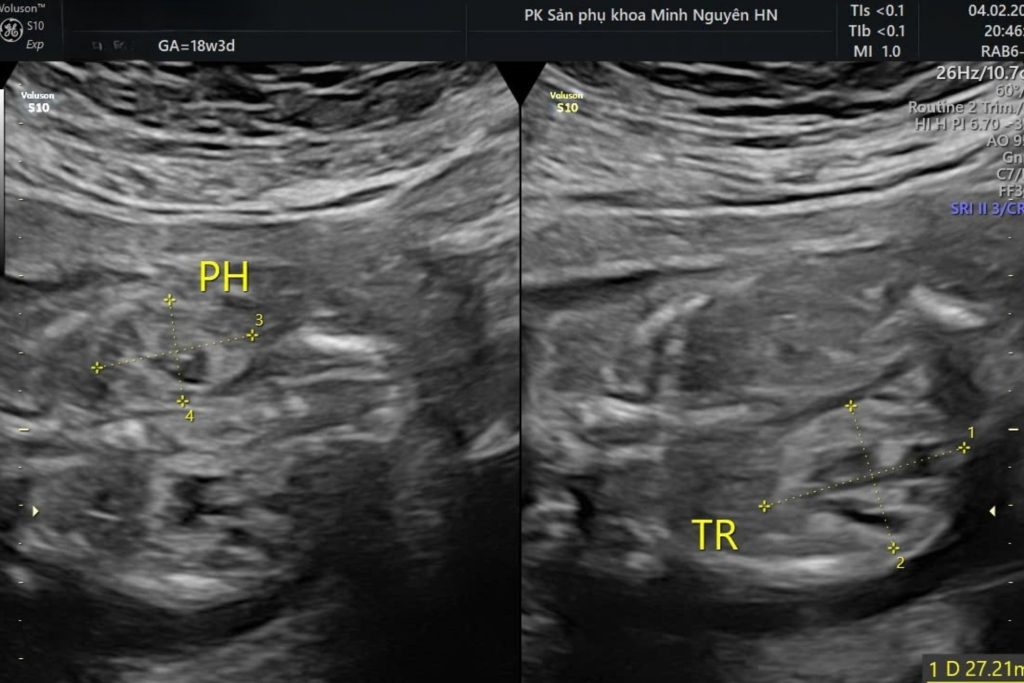

Chị H. đến phòng khám Dr Tú y học bào thai vào một buổi chiều muộn khi thai được 21 tuần. Trên tay chị là tờ kết quả siêu âm vừa làm buổi sáng. Dòng mô tả ghi thận phải tăng âm, cấu trúc không đồng nhất, cấu trúc không đồng nhất,nghi loạn sản thận.

Bác sĩ bắt đầu bằng việc xem lại toàn bộ hình ảnh siêu âm mà chị mang theo. Sau đó siêu âm lại một cách cẩn thận, dựng các mặt cắt chuẩn của hai thận, đo kích thước từng thận, quan sát bàng quang và đánh giá lượng nước ối.

Giai đoạn 20–24 tuần là thời điểm thận đủ lớn để quan sát rõ trên siêu âm. Bác sĩ có thể nhận diện:

- Thận tăng âm thai nhi

- Thận có nang

- Cấu trúc không đồng nhất

- Ranh giới vỏ tủy mờ

- Kích thước bất thường

Siêu âm giúp đánh giá hình thái nhưng không đo trực tiếp chức năng thận của thai nhi. Vì vậy nhiều trường hợp chỉ được ghi nghi Loạn sản thận và cần theo dõi thêm.